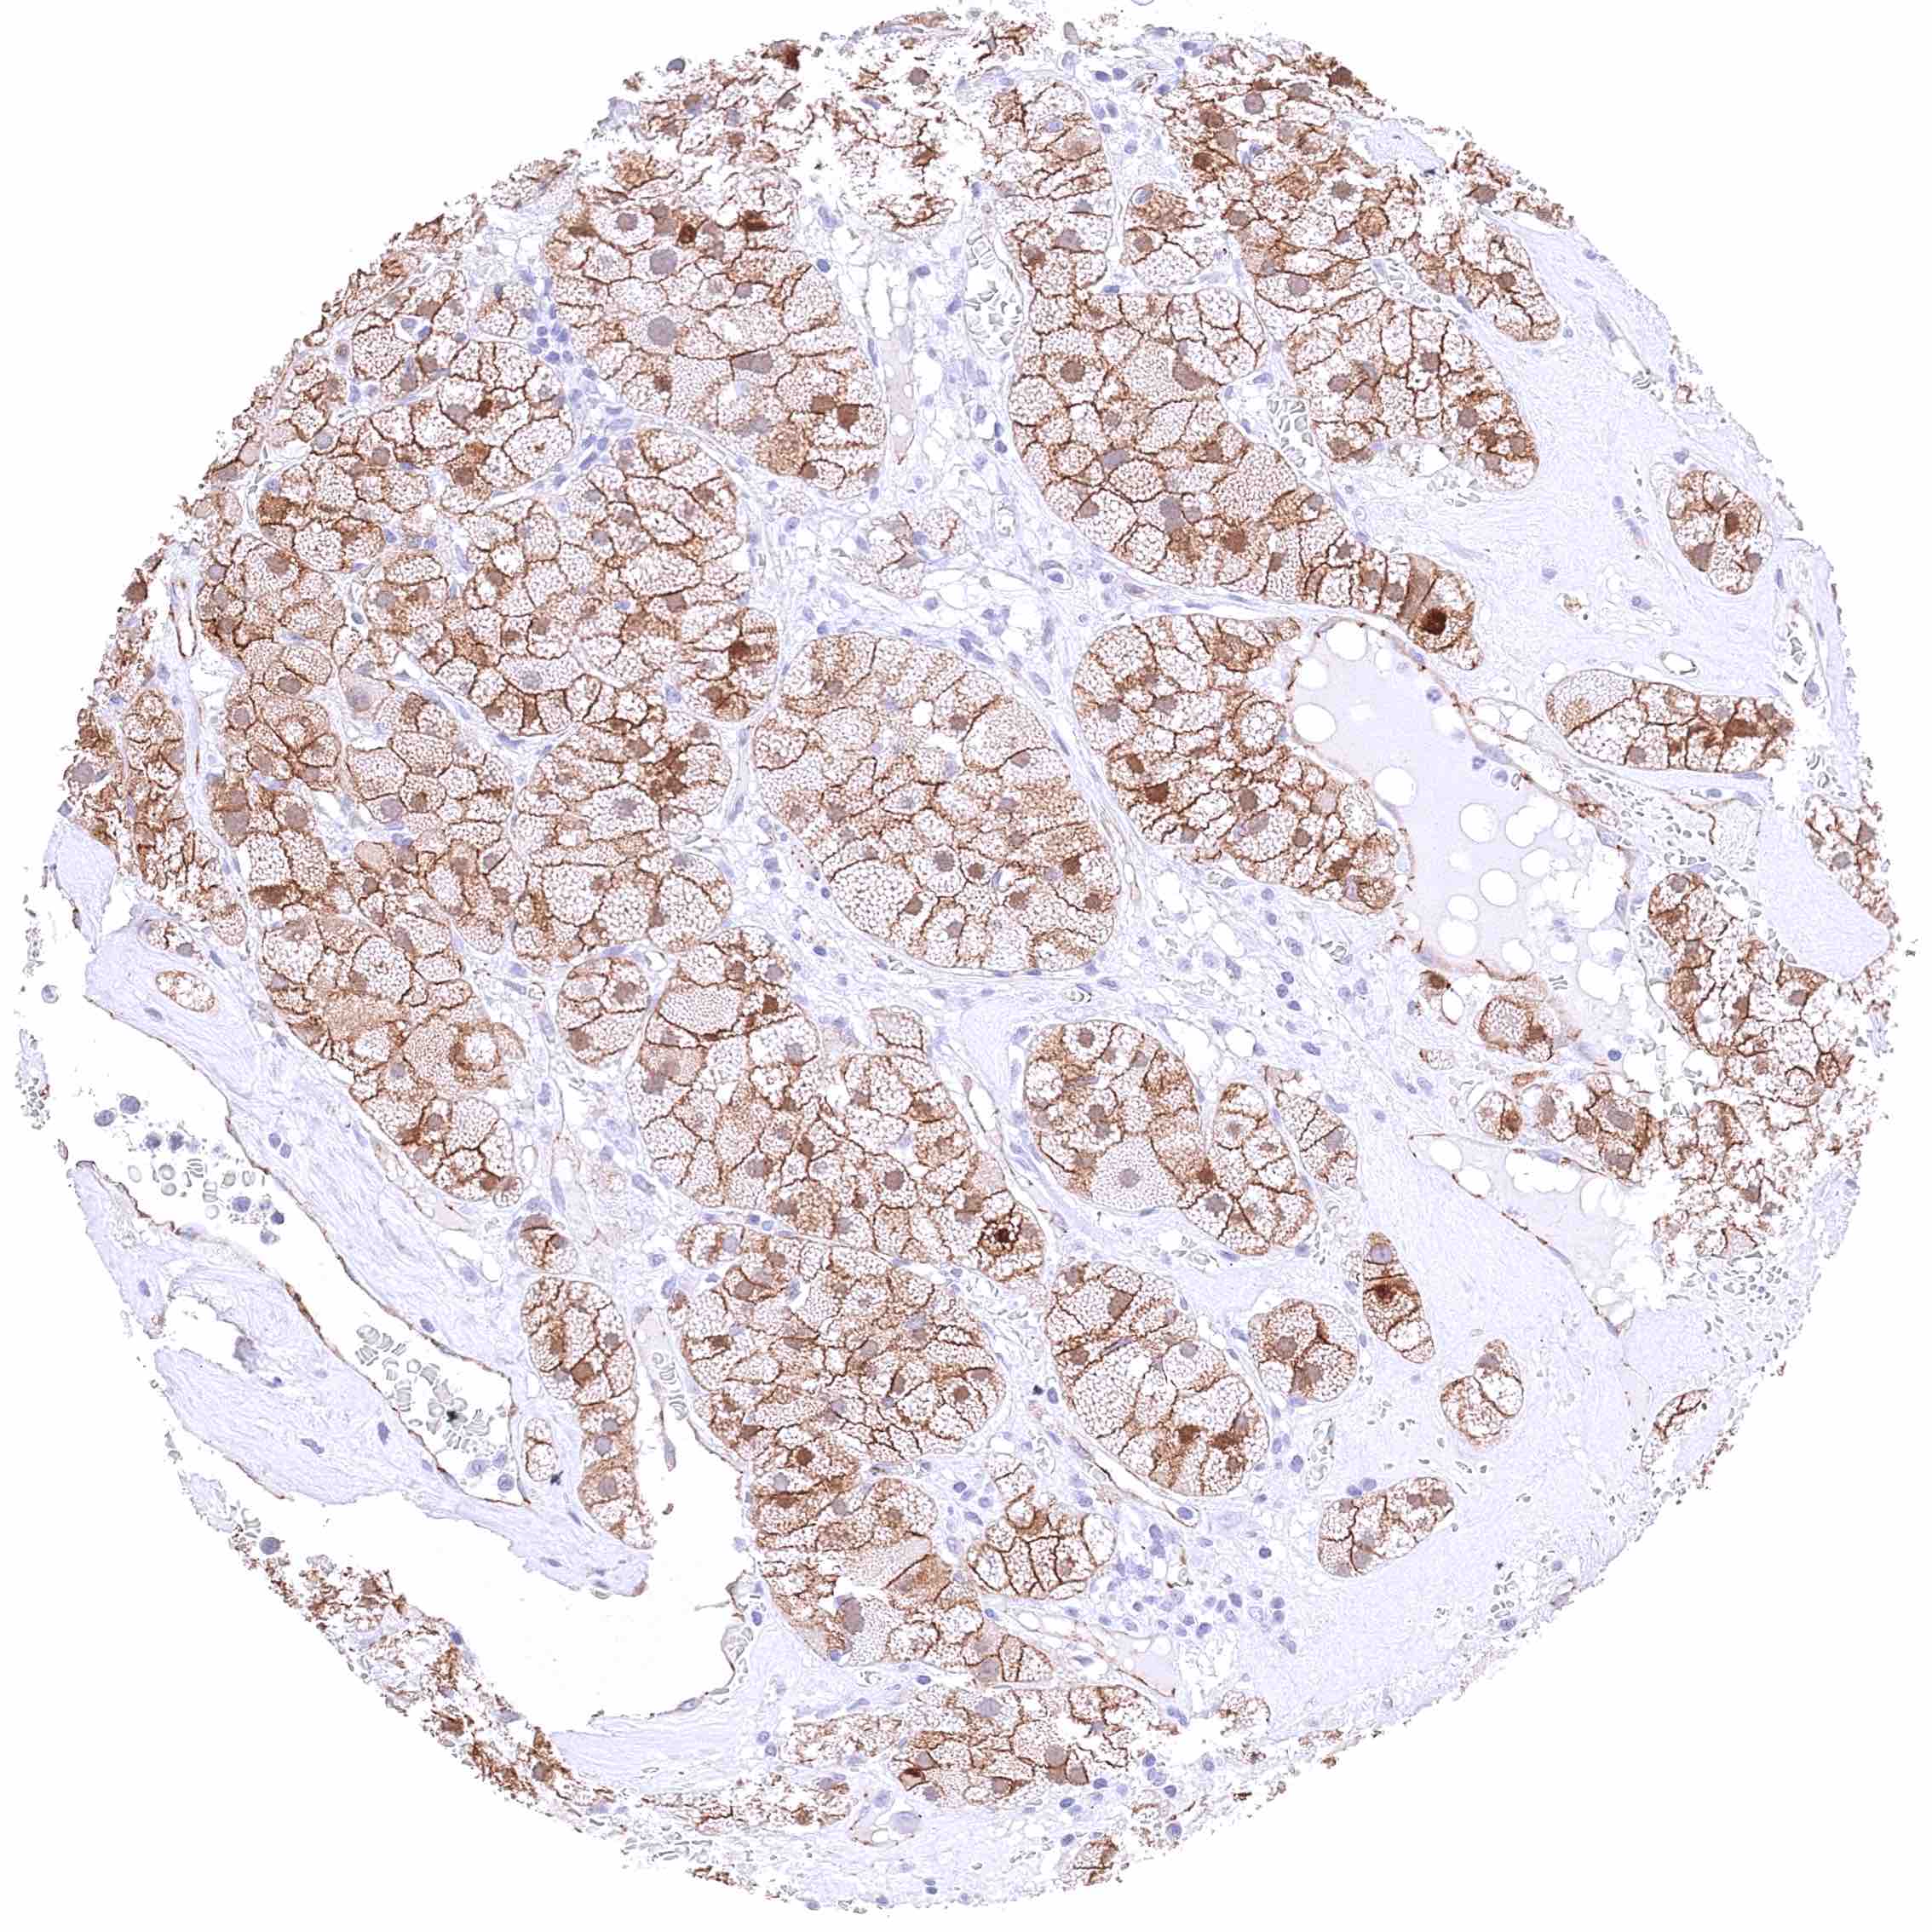

Pancreas – Ductal adenocarcinoma with strong membranous β-Catenin staining of tumor cells possibly accompanied by a mild cytoplasmic positivity.

Pancreas – Neuroendocrine tumor with strong membranous β-Catenin positivity of tumor cells.

Pancreas – Neuroendocrine tumor with weak membranous, moderate cytoplasmic, and strong nuclear β-Catenin staining of tumor cells.